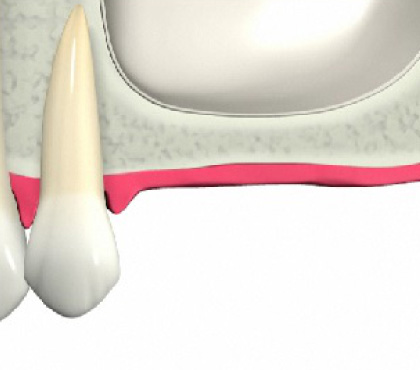

奥歯を失ったら

インプラント

外科処置をしてインプラントを埋入します。

奥歯へのインプラント